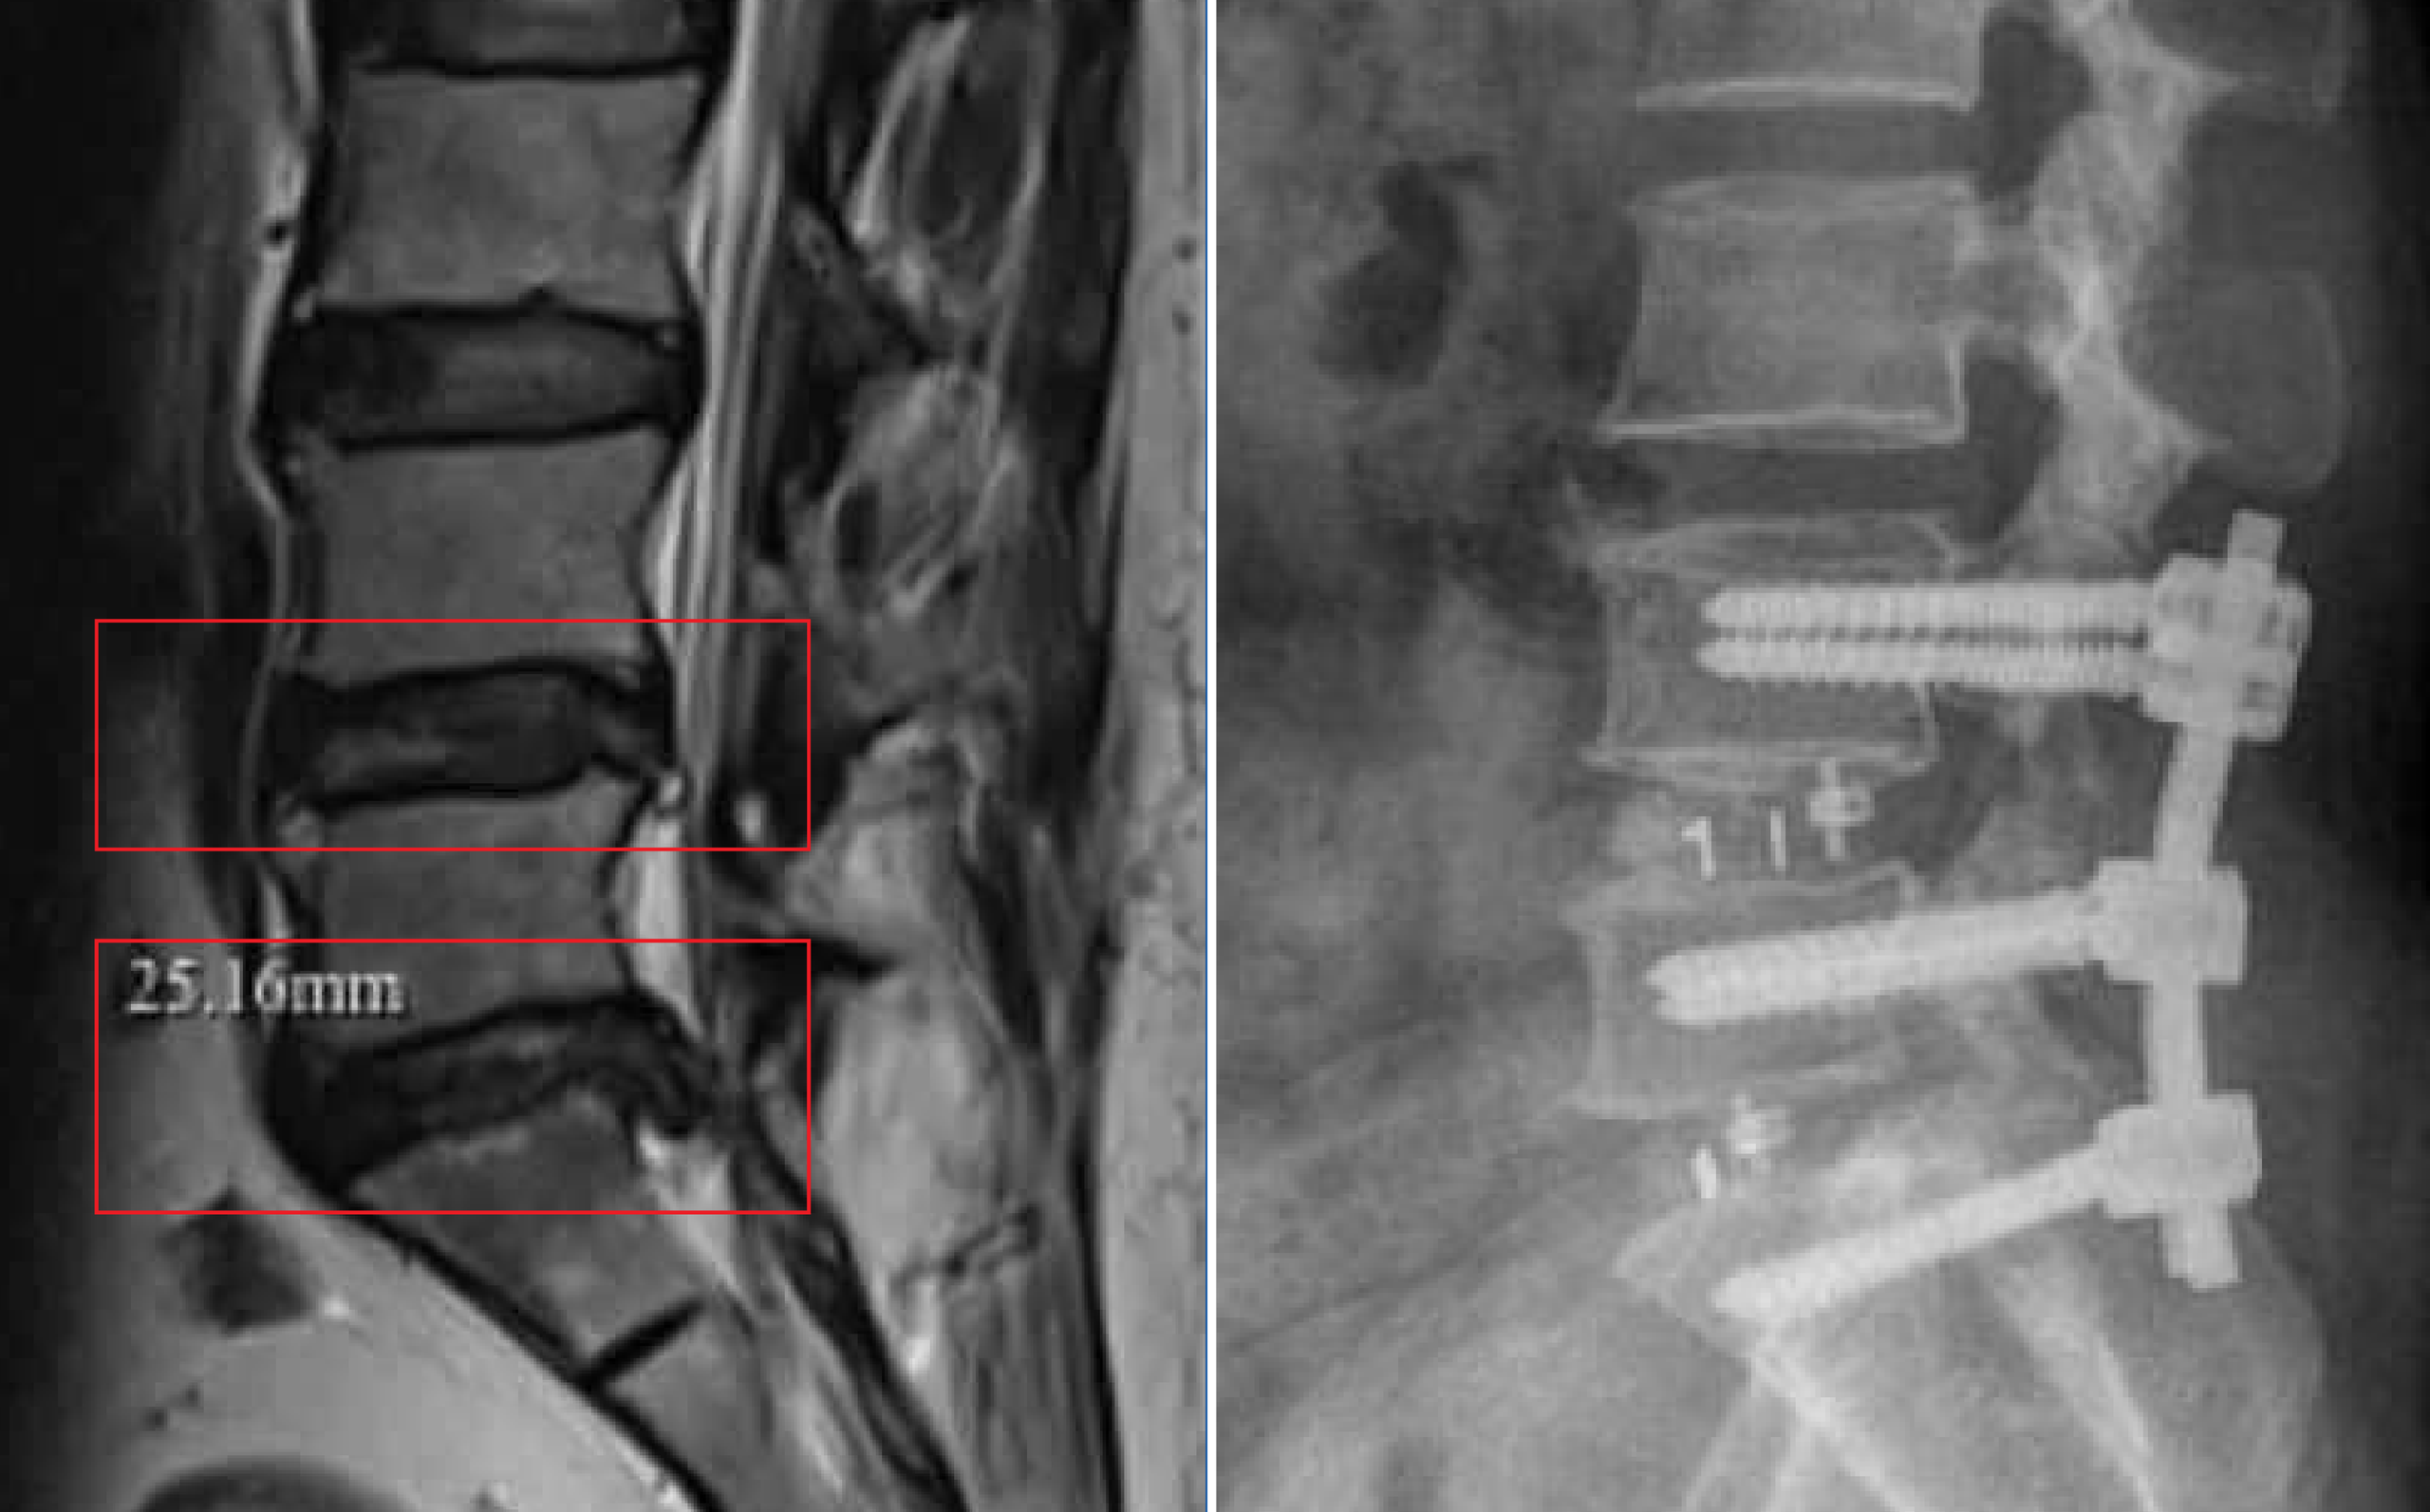

Cột sống của người bệnh trước và sau phẫu thuật

Kết quả chẩn đoán MRI cho thấy, bà N. bị thoái hóa cột sống kèm thoát vị đĩa đệm đa tầng (L4–L5; L5–S1) gây chèn ép rễ thần kinh cột sống – nguyên nhân khiến bà đau lưng nhiều năm và nguy cơ liệt chi nếu không được điều trị kịp thời.

Sau khi đánh giá toàn diện, ê-kíp phẫu thuật đã lựa chọn phương pháp TLIF nhằm giải phóng rễ thần kinh bị chèn ép, đồng thời tái tạo sự vững chắc cho cột sống.

Mua Hàng với Shopee

Đáng mừng, 2 ngày sau phẫu thuật, bà N. đã có thể tự ngồi dậy và bắt đầu chương trình phục hồi. 1 tuần sau, bà xuất viện với sức khỏe ổn định, tự sinh hoạt và vận động nhẹ nhàng.